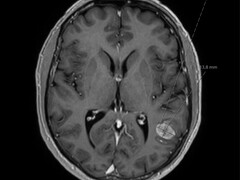

Beeldquiz

Stel je diagnose op basis van een foto. De wekelijkse beeldquiz van het NTVG is een leuke manier om je kennis snel te testen en te vergelijken met anderen.